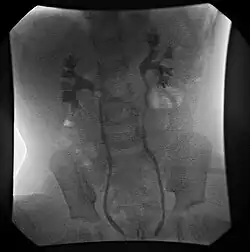

| Ultrasound image showing abnormal vesicoureteral junction and dilated distal ureter resulting in primary vesicoureteral reflux (VUR). | |